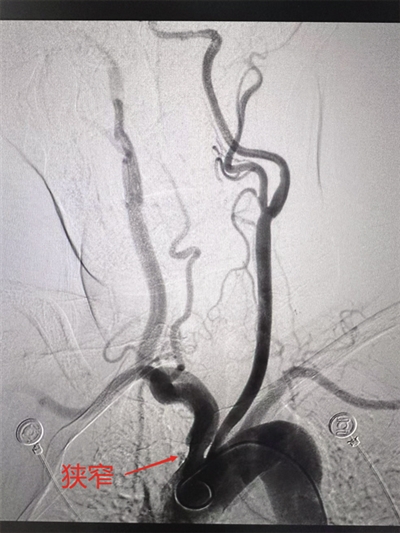

患者脑血管局部影像显示狭窄。

患者女性,76岁,因发现左侧肢体活动不利、言语含糊4个多小时入院,头颅磁共振确诊为急性脑梗死。经MDT团队紧急会诊,决定为其行脑血管造影术,以明确脑血管是否狭窄及狭窄程度。通过脑血管造影,不仅清晰发现患者头臂干动脉起始部狭窄、颅内动脉粥样硬化、右侧颈内动脉后交通段存在“定时炸弹”——动脉瘤。此次造影为患者制定更合理的治疗方案提供了科学的依据。